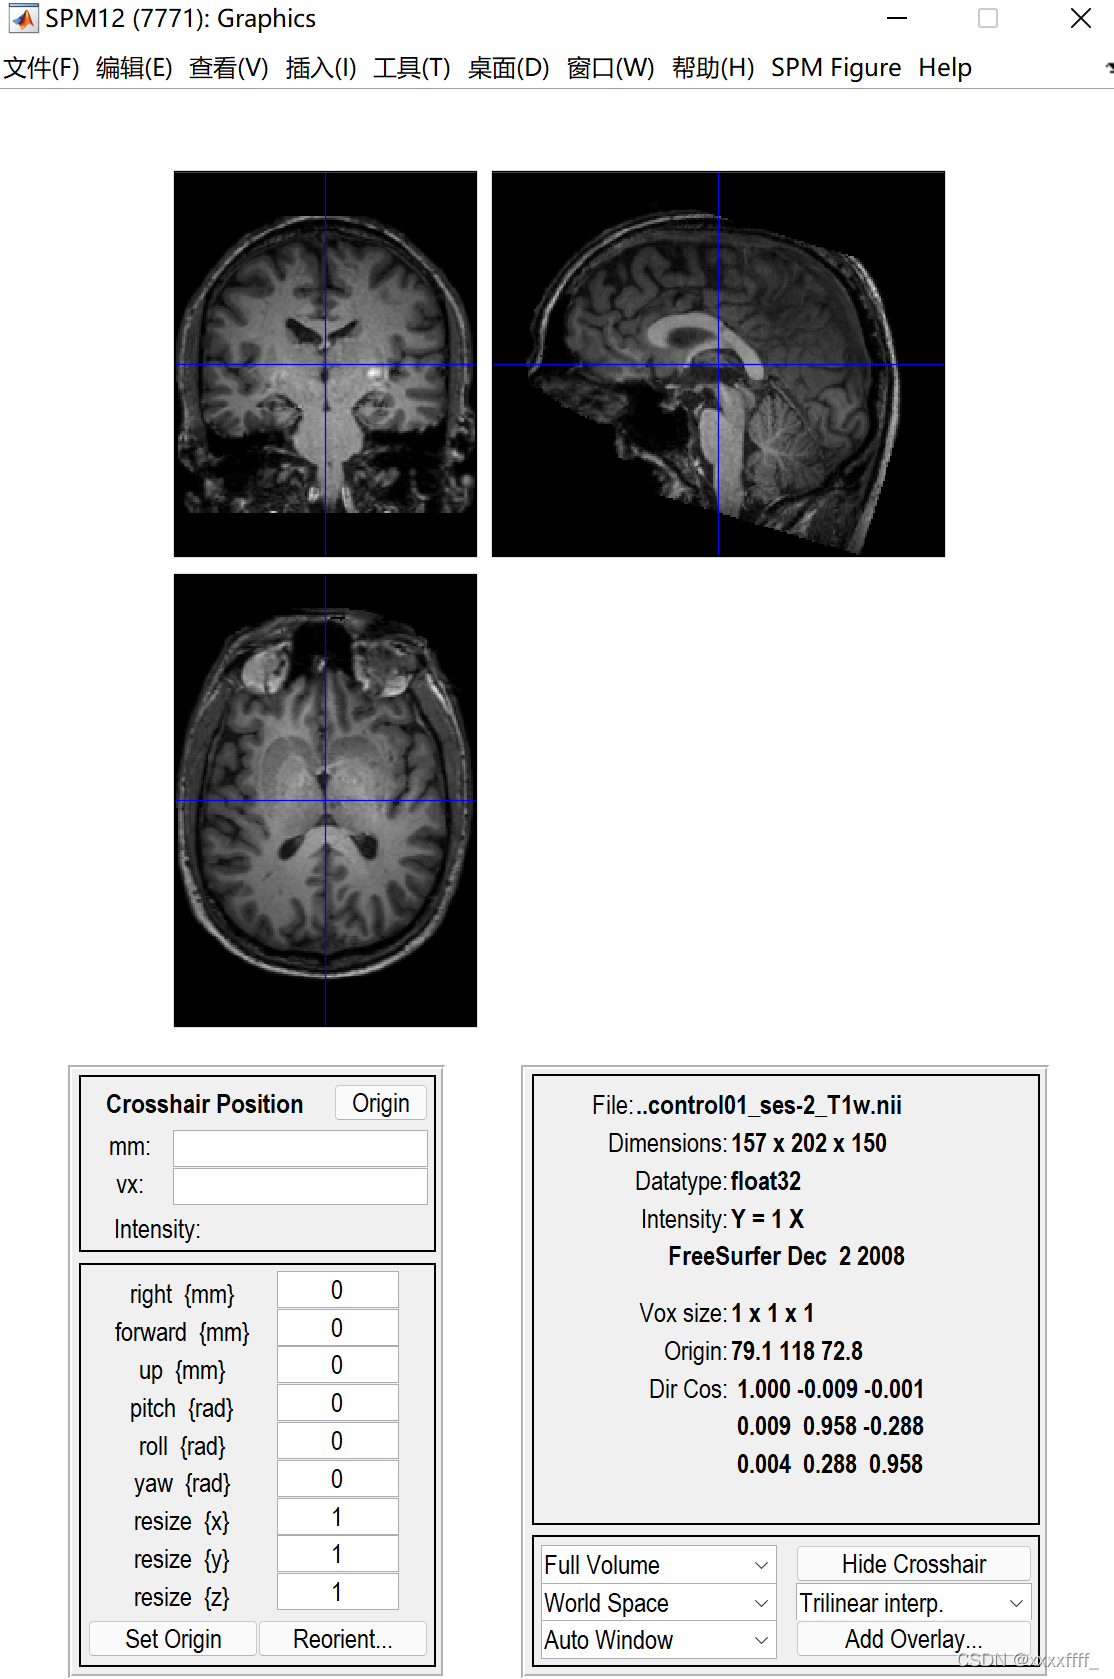

然后就选择自己的数据里的T1结构像。

一个这样的页面,我们可以看到一个蓝色的十字线,这个线的交叉点就是我们要调整的地方,手动将交叉点放在大概下图这个位置(就是前联合的位置),前联合的位置怎么确定可以去查一下,网上有很多教程。我的理解就是大概在下图这个红色的圆里。点一下set origin之后就会出现坐标位置。然后一定要点击一下Reorient,才算是调整成功了。